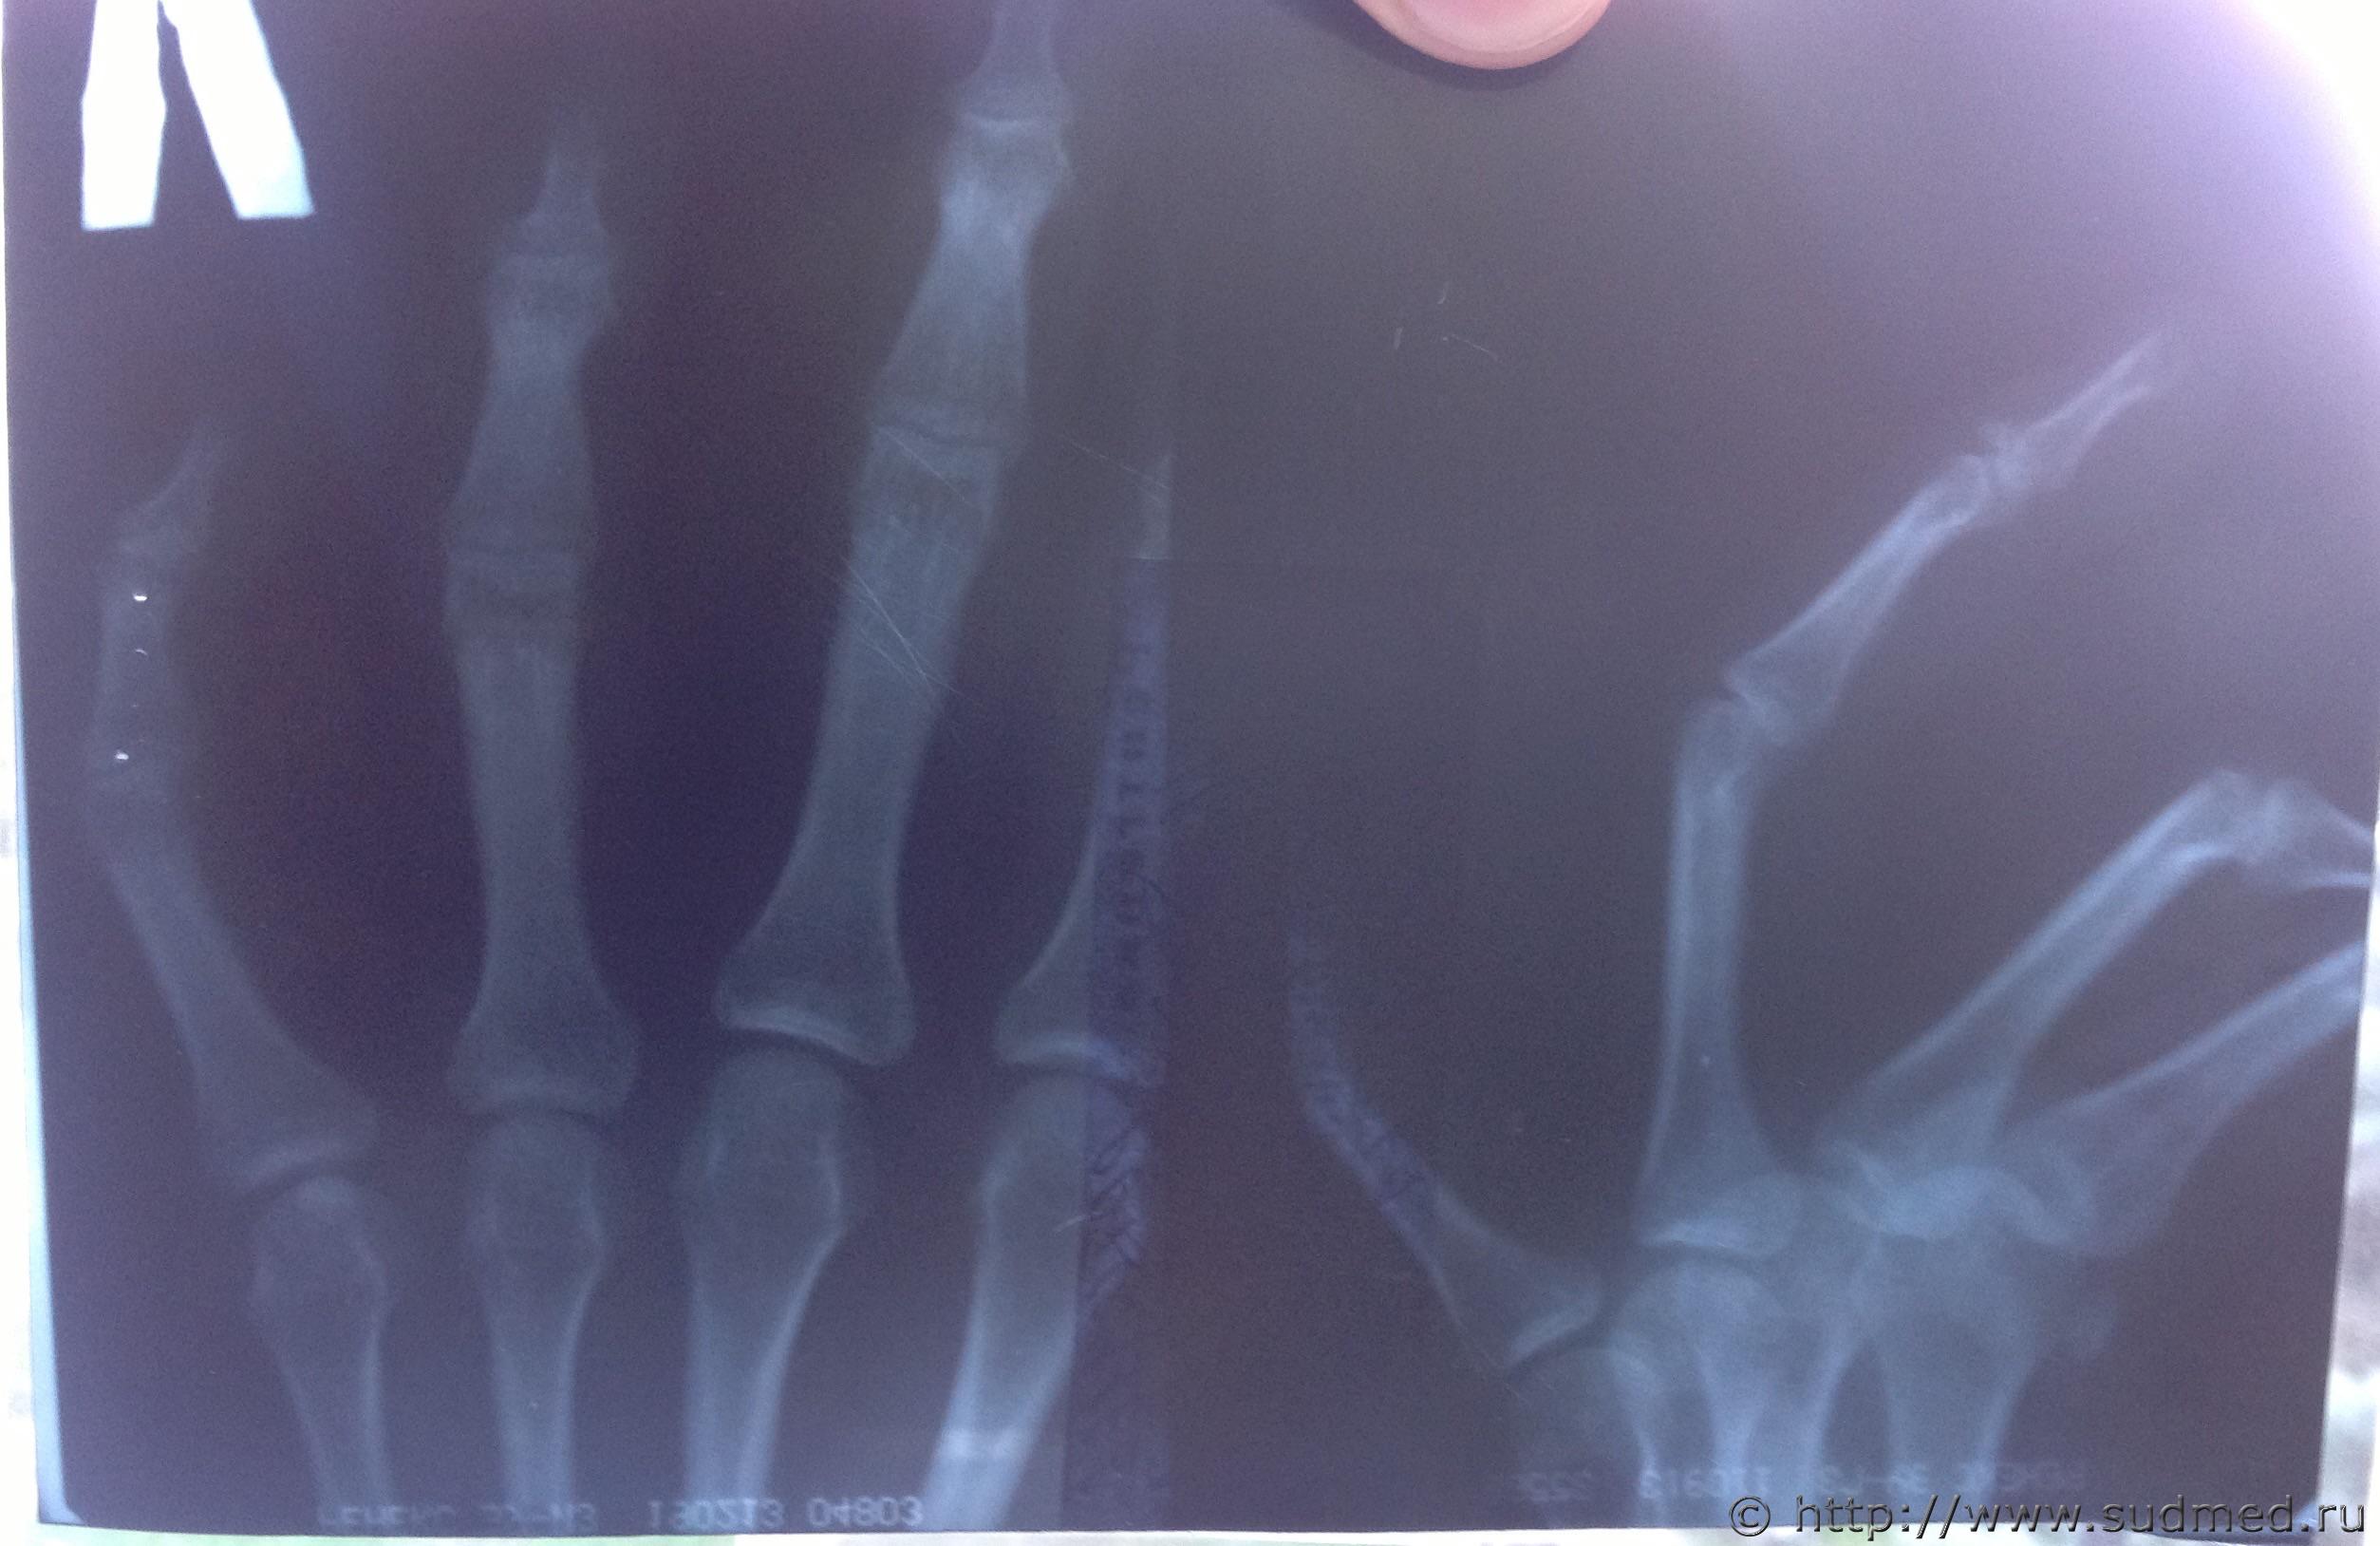

Судебная медицина - Прикрепленное изображение Судебная медицина - Прикрепленное изображение Судебная медицина - Прикрепленное изображение Судебная медицина - Прикрепленное изображение Судебная медицина - Прикрепленное изображение Думаю эти лучше по качеству изображения.

Да, эти снимки немного лучше. Как мне видится по этим неважнецким снимкам: отрывной внутрисуставной перелом в области задней поверхности основания дистальной (ногтевой) фаланги четвертого пальца с удовлетворительным стоянием отломков, без признаков консолидации (на дату съемки - на фото она закрашена).

Такой перелом характерен для непрямого действия повреждающей силы при тупой травме: при резком насильственном сгибании ногтевой фаланги, находящейся в состоянии напряженного разгибания либо при сильной и некоординарованной попытке разгибания ногтевой фаланги против действия внешней силы, вызывающей сгибание во втором межфаланговом суставе этого пальца (сустав между средней и ногтевой фалангами).

Если упасть на кончик этого напряженного и разогнутого пальца таким образом, что он начал сгибаться под влиянием массы тела упавшего человека, то может быть такой перелом. Аналогично - от удара по кончику напряженно разогнутого пальца или при ударе кончиком напряженно разогнутого пальца (например, у баскетболистов такое бывает, когда неудачно попадают пальцем по мячу).

Если схватить за кисть, за этот палец и резко надавить на ногтевую фалангу напряженно разогнутого этого пальца, то такой перелом тоже может возникнуть.

Может такой перелом быть получен и при попытке насильственного сгибания этого пальца (например, рукой другого человека), когда пострадавший пытается не дать согнуть свой палец, чрезмерно резко напрягает сухожилие и происходит отрыв костного фрагмента в месте, где сухожилие разгибателя крепится к ногтевой фаланге.

По медицинским данным невозможно однозначно определить, как мог быть сформироваться этот перелом - при падении, ударе или в результате "хватания за руку". Это должен установить суд.